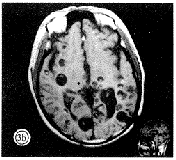

T1WI+C对病变的显示率更高,达100%,可清楚地显示头节,囊壁的厚薄,头节的存在与囊壁厚薄的关系:显示头节的病例囊壁多为薄壁,少见有水肿,与文献[3]相符:T1WI+C对于发现病变,病变数目,尤其对于发现脑室内病变有其独到之处,直径15~25mm的病多位于脑室内,文献[4]相符。但对灶周水肿的显示较T2WI不明显(图3)。

图3 (a、b)T1WI上表现脑实质内及脑室内、桥脑内见各个大小不等囊状低信号,部分病灶内可见点状高信号;(c) T2WI上表现前述病变为高信号,少数病灶内见点状低信号;(d) T1WI+C 上部分病变见环形强化、厚薄不均的壁及头节,部分头节轻度强化。